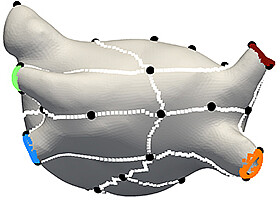

- Medicine and healthcare

- Simulation and data processing

- Software and IT

- Automation / IT

- Measurement technology

Heart models for the treatment of atrial fibrillation

Individual, digital heart models can be used to test therapies in order to select the one that promises the greatest success. A KIT method creates patient-specific virtual images of the heart from clinical data.